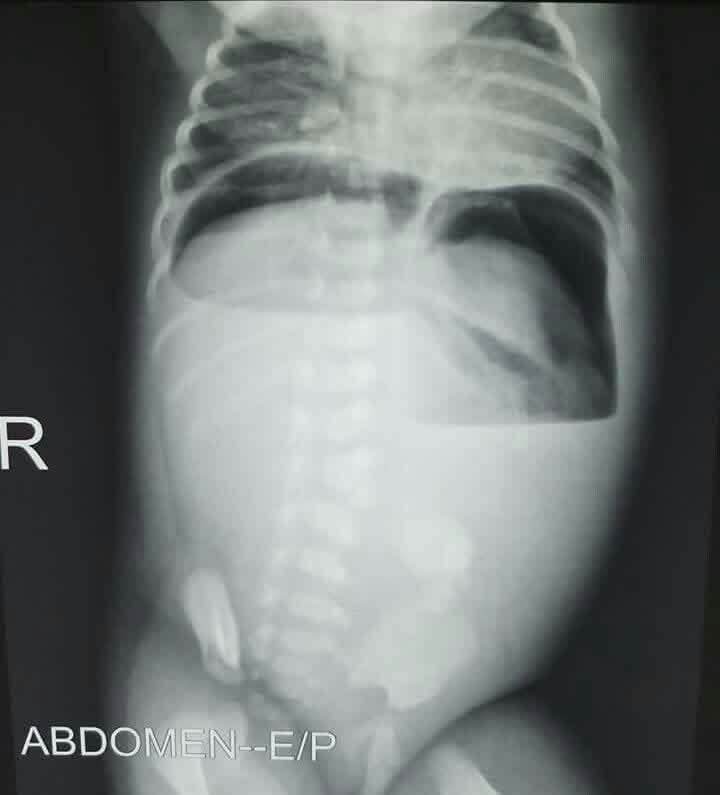

ABDOMINAL PAIN + DISTENTION + COFFEE BEAN SIGN. Choose the correct option A. Sigmoid volvolus B. Gastric Volvolus C. Midgut Volvolus D. I don’t know E. I don’t care #Xray

DrAyubaD's tweet image. ABDOMINAL PAIN + DISTENTION + COFFEE BEAN SIGN.

Choose the correct option

A. Sigmoid volvolus

B. Gastric Volvolus

C. Midgut Volvolus

D. I don’t know

E. I don’t care

#Xray